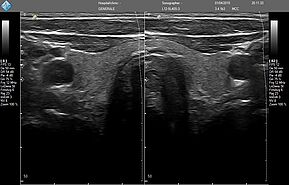

- MicrUs Pro-L40S (линейный, 5-12 МГц, 40 мм)

MicrUs Pro-L40N (линейный, 5-12 МГц, 40 мм, производительная версия)

MicrUs Pro-C60S (конвексній, 2-5 МГц, R60 мм)

ЗДЕСЬ Вы можете посмотреть реальные кинопетли с аппарата УЗИ MicrUs Pro.